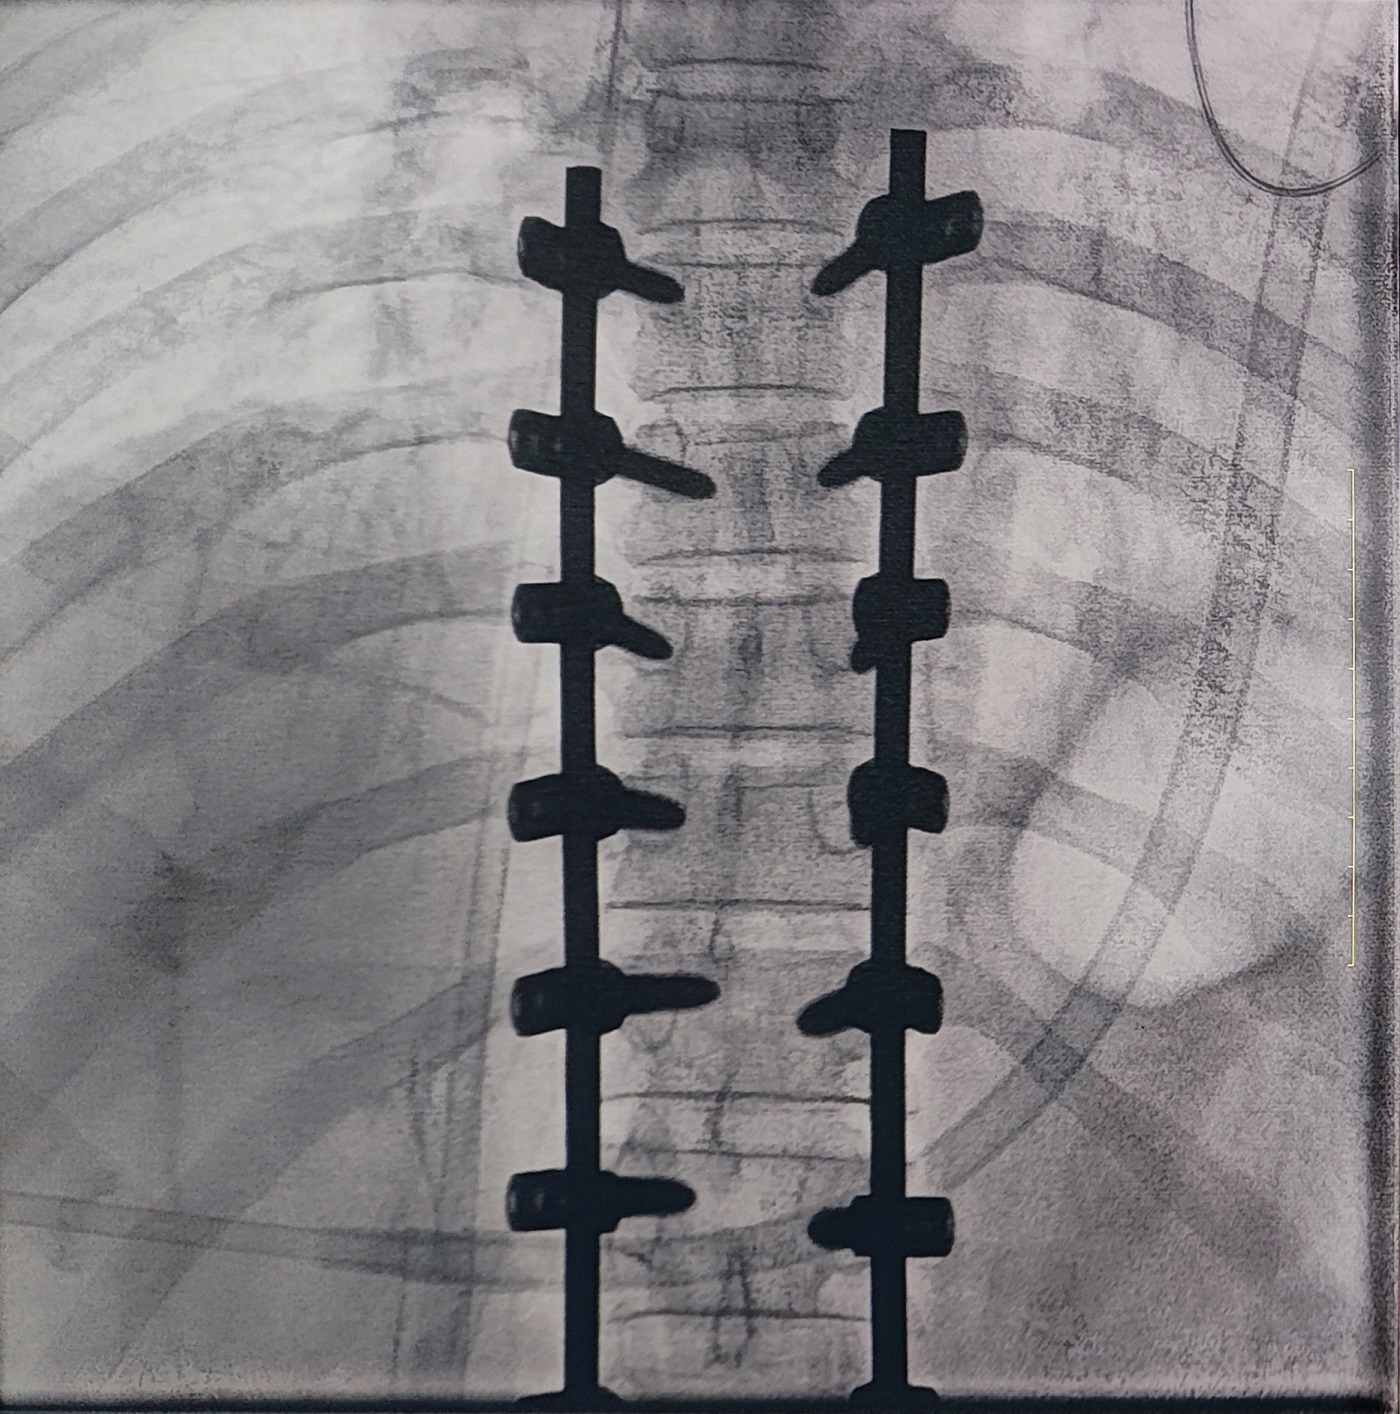

一場(chǎng)脊柱手術(shù)中,醫(yī)生需要拍攝跨越7個(gè)節(jié)段的脊柱影像,由于曝光的視野較大,常規(guī)視野的C形臂通常需要拍攝2-3次,普愛醫(yī)療大平板一體式C形臂30CM*30CM的“大視野”,輔助醫(yī)生一次性完成了7個(gè)節(jié)段的拍攝。最終,醫(yī)生在高清影像的輔助下完成了14枚螺釘?shù)木珳?zhǔn)定位、置入。

大視野,不僅意味著醫(yī)生可以更快,獲取更全面的影像信息,做出精準(zhǔn)判斷,無(wú)需多次拍攝定位,也顯著地降低了患者接受的輻射劑量。